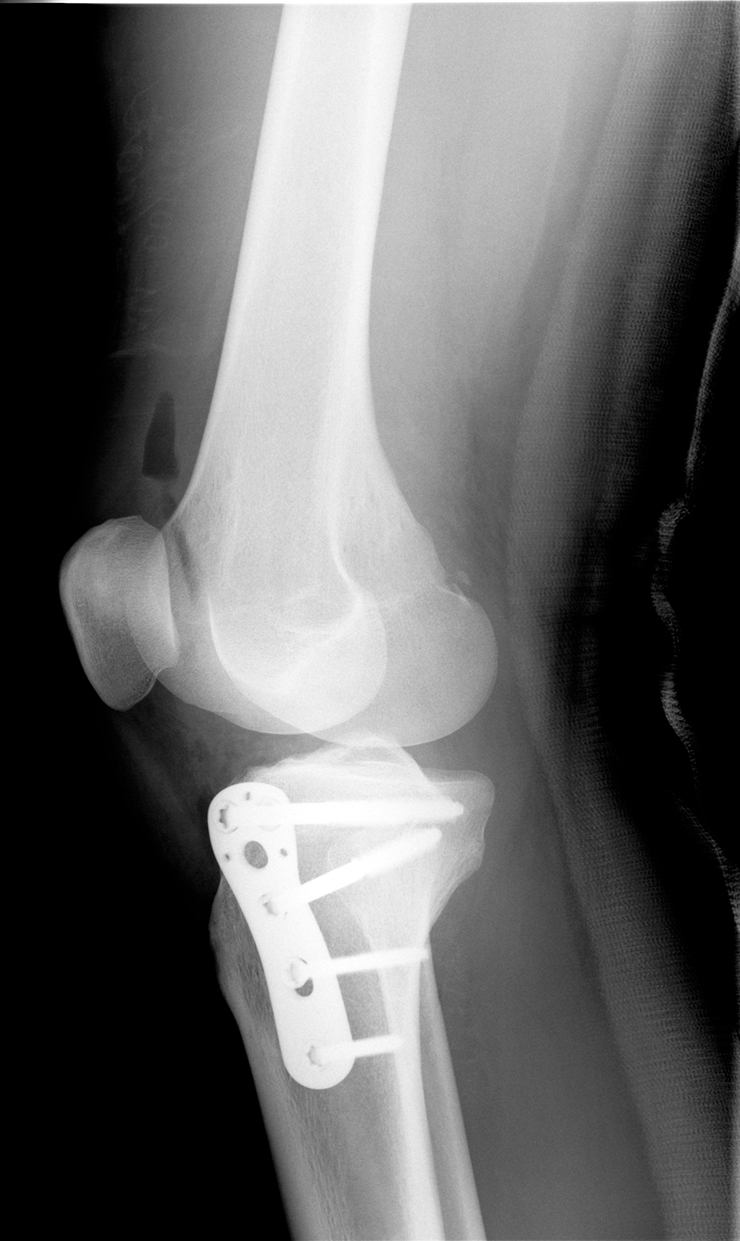

この仕組みからわかるように、「磁気を乱す要素があるとMRI検査は受けられない」ということになります。例えば骨折治療でボルトを使用している方、歯列矯正で金属の矯正器具を使っている方などが「MRI検査を選べない人」に該当します。